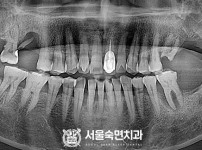

임플란트-전후사진3